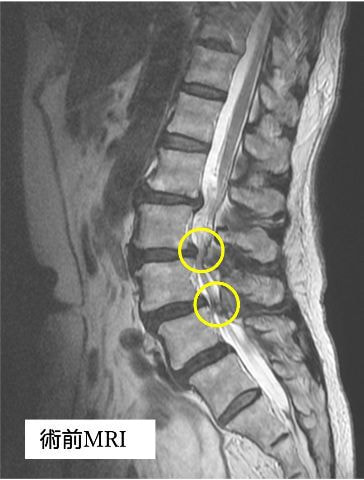

手術の2年ほど前から腰から両殿部痛、下肢後面のしびれが出現し、他院にて腰部脊柱管狭窄症の診断を受けました。徐々に症状は増悪し、手術前は間欠性跛行(※)で長距離の歩行が困難となり、家事を行う際も何度も休憩が必要な状態でした。また、痛みを避けようとするためにかばった姿勢(写真1)となり、筋力低下・可動域制限を認めている部分がありました。その後、手術希望にて当院を受診され、腰椎後方除圧椎体固定術(cortical Bone Trajectory:CBT)が行われました。